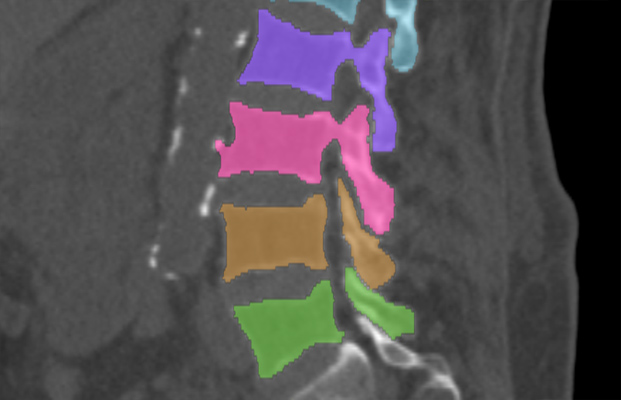

We trained and evaluated the method with five sets of CT and MR scans that visualize the spine. Reference segmentation masks for four of these datasets are publicly available, which allowed for a comparison with other publications that used the same data. Examples of images from the datasets are shown in Figure 3.

Similar performance was achieved for vertebra segmentation in various CT datasets with an average Dice score of and for vertebral body segmentation in an MR dataset with an average Dice score of . Surface distances were lower on CT images compared to MR images ( vs. ), however, there were also fewer training scans available in the MR dataset. Figure 4 illustrates the magnitude of differences of the automatic segmentations from the ground truth segmentations.

(a) Low-dose chest CT

(b) Lumbar spine CT (xVertSeg.v1 dataset)

(c) Lumbar spine MR